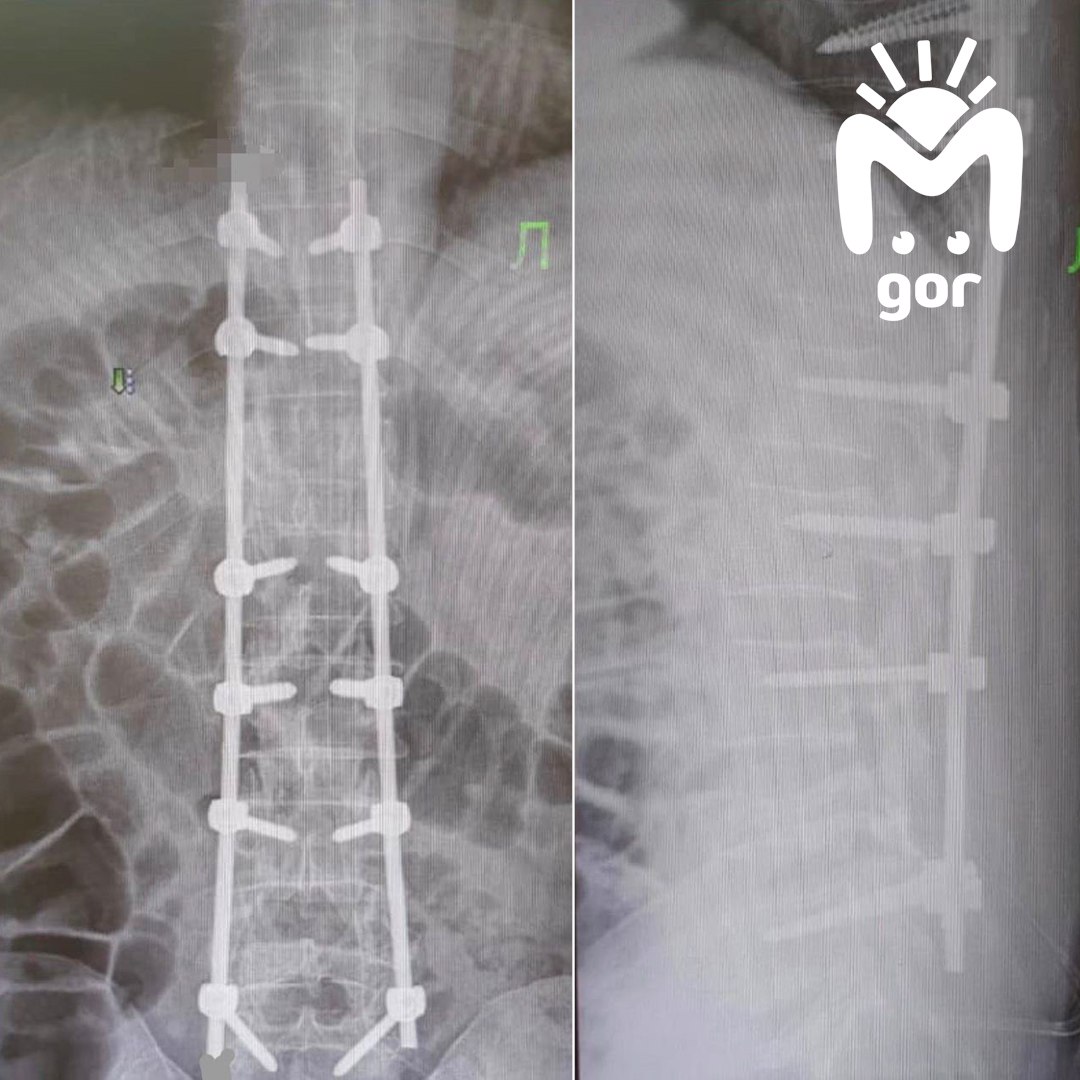

Нейрохирурги провели сложную операцию: убрали давление на спинной мозг и собрали позвоночник как конструктор — поставили титановые винты и стержни. Уже через пару дней после операции их подопечный смог встать и пройтись по палате. Помогли и современное оборудование, и ювелирная точность хирургов.